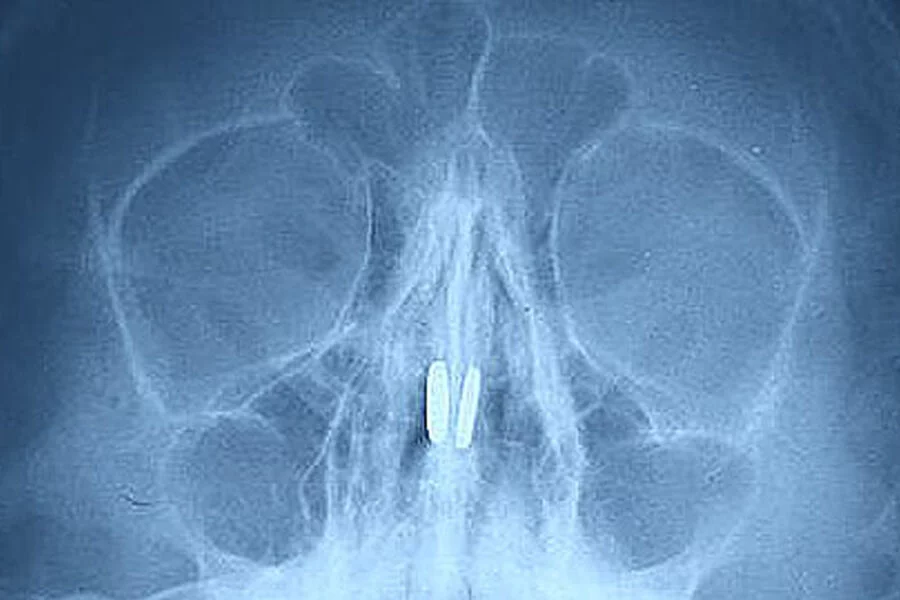

Nijni Novqorod vilayətində həkimlər uşağın burnundan maqnit toplarını çıxarıblar.

News24.az bildirir ki, balaca xəstə burun nahiyəsində ağrı və tənəffüs problemi şikayəti ilə tibb müəssisəsinə aparılıb. Müayinə zamanı oyuncaqdan olan maqnitlər burun çəpəri vasitəsilə bir-birinə çəkilən burun sinuslarında aşkar edilib.

Yad cisimlər xüsusi çəngəl ilə çıxarılıb, oğlan heç bir ciddi xəsarət almayıb.